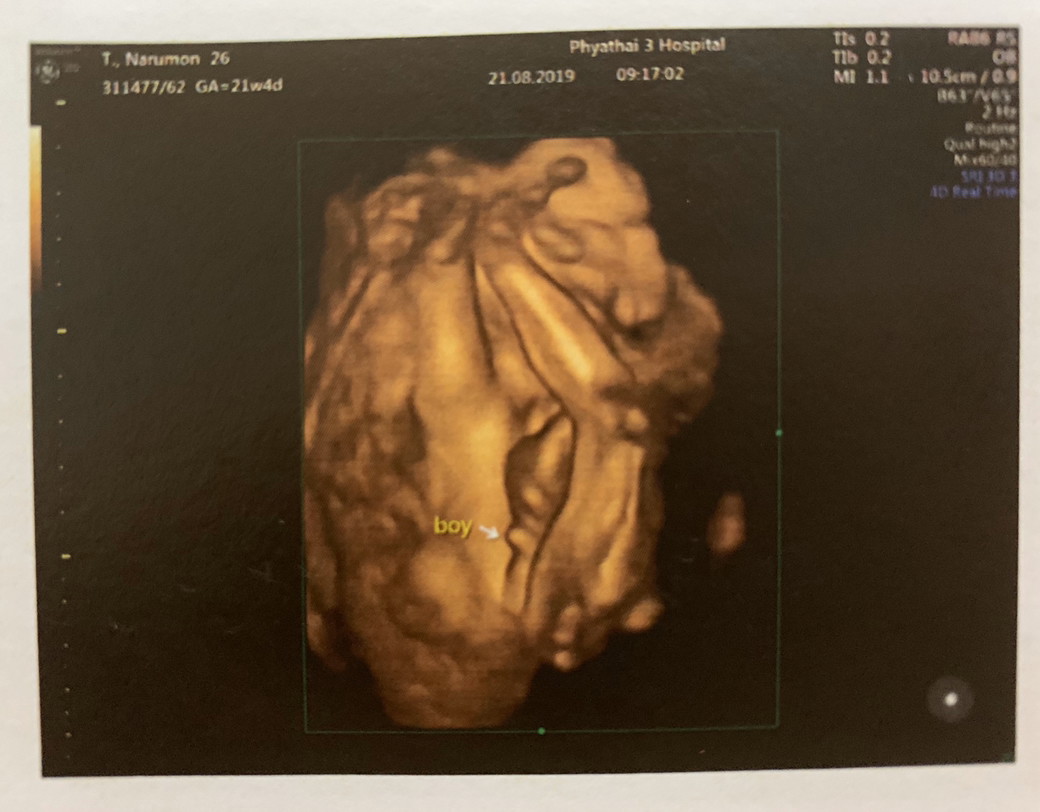

จู๋เด่นมาเลยค่ะแม่

กระจู๋ผมใหญ่คับ😂😂

โด่ชัดเจนมากคร้า555